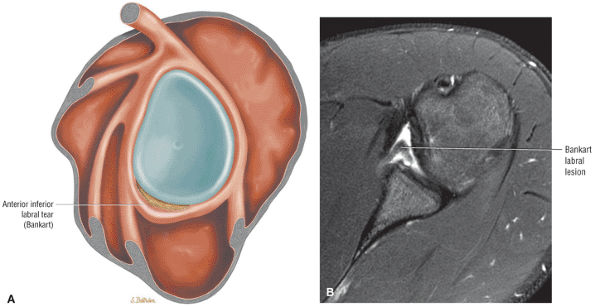

Partial-thickness articular surface tears are seen as a detachment of cuff fibers at their footprint attachment to the greater tuberosity both on ABER MR arthrograms and routine phased-array coil imaging of the shoulder.

![]() |

|

FIGURE 8.175 ● (A) Adherence of the retracted rotator cuff to the coracohumeral ligament. (B) Coronal FS PD FSE image showing the thickened coracohumeral ligament associated with torn and retracted supraspinatus. (C) A corresponding arthroscopic view shows the articular surface of the avulsed supraspinatus tendon (S; arrow). B, biceps tendon; HH, humeral head; Sub, subacromial space.